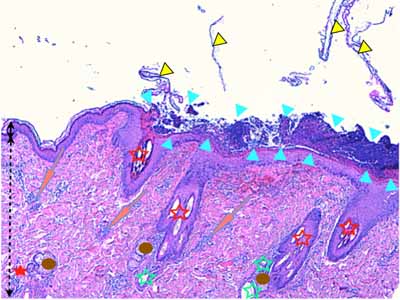

Photo 9 (Hémalun Eosine X 40) : Les pustules sous-cornées qui parsèment l’épiderme,

peuvent ponter l’abouchement de plusieurs follicules pileux voisins.

Légendes de la Photo 9 :

- Double flèche noire : épiderme

- Double flèche pointillée noire : derme

- Pointes de flèche turquoise : délimitation de la pustule intra-épidermique sous-cornée qui ponte l’abouchement de trois unités folliculo-sébacées

- Pointes de flèche jaune : toit rompu de la pustule (fines lamelles de kératine orthokératosique)

- Cercles marrons : glandes sébacées

- Étoiles rouges pleines : vaisseaux sanguins

- Étoiles rouges vides : follicules pileux

- Étoiles turquoises : glandes sudorales apocrines épitrichiales

- Flèche orange : infiltrat dermique de topographie péri-vasculaire